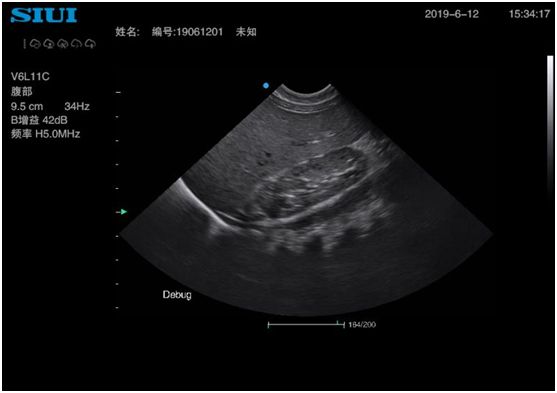

3、小儿腹痛可以做什么超声检查?

(1)肠系膜淋巴结:小儿急性肠系膜淋巴结炎痰状为发热、腹痛、呕吐,部分伴腹泻。小儿肠系膜淋巴结炎为良性反应性增生,超声可以清晰的发现肿大的淋巴结。

(2)阑尾:急性阑尾炎超声可以看到肿大的阑尾,其周围可伴有肿大的淋巴结。对于两者的鉴别,快捷方便无创性的超声检查可以发挥其优势。